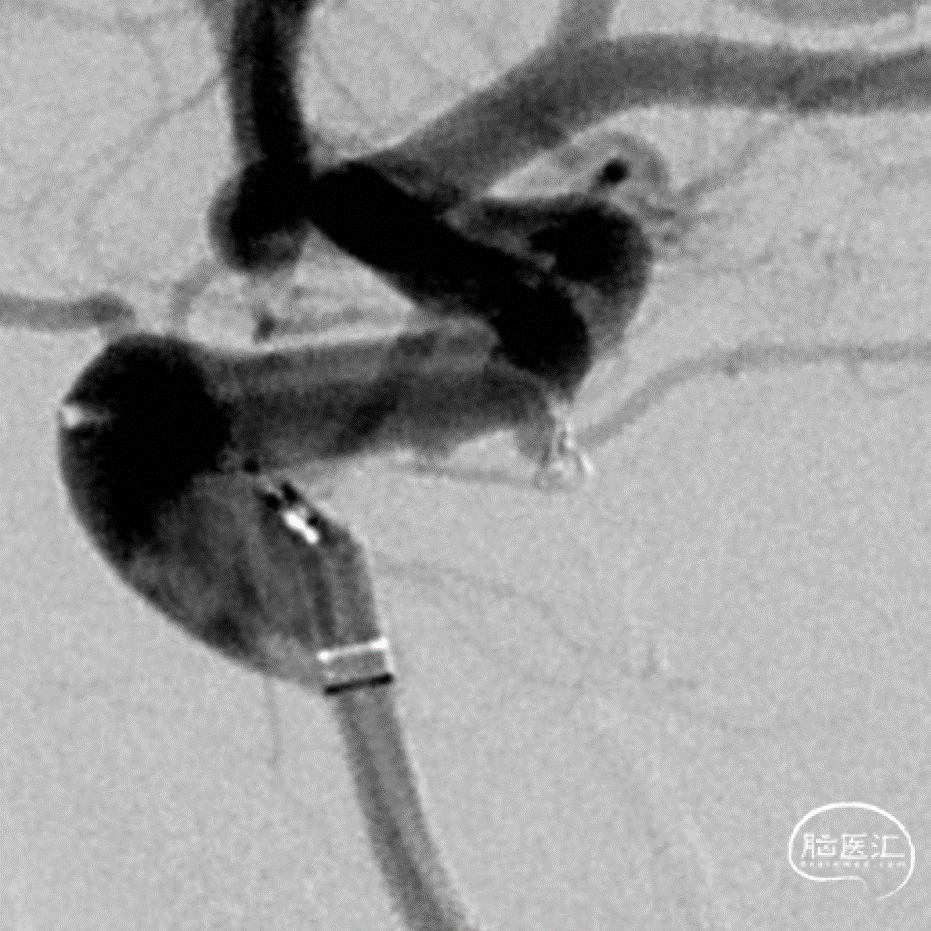

急性期治疗

治疗过程

工作角度造影

Roadmap

微导管超选

Galaxy G3 MINI 1mm*1cm的mini(强生)

术后情况/术后即刻:动脉瘤不显影

术后3D重建:动脉瘤不显影,载瘤动脉通畅